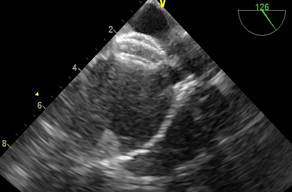

En subcostal 4 cámaras se observa CIA de 7 mm de diámetro con shunt de izquierda a derecha. (Figuras 2,3,4)